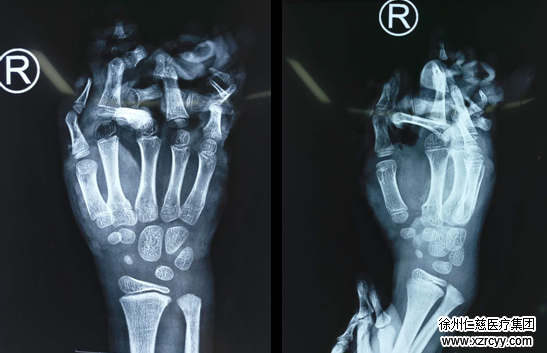

三个月后,小虎再次来到医院,当他见到黎章灿医生,第一句话就是“叔叔,我想要5根手指”,在完善了各项检查后,黎医生为小虎进行第一次分指手术,手术很顺利,2周后小虎顺利出院。

二次分指手术,让小虎3指成功变5指

在做好各项术前准备后,黎章灿医生为小虎进行了第二次分指手术,术后小虎右手被绷带包扎,见到黎医生第一句话就问:“叔叔,几只手”,黎医生告诉小虎,这次变成了5根手指,小虎听到后兴奋的叫了好久。术后小虎通过系统的康复锻炼,现在已经和其他小朋友一起走进校园,还能用右手写字。